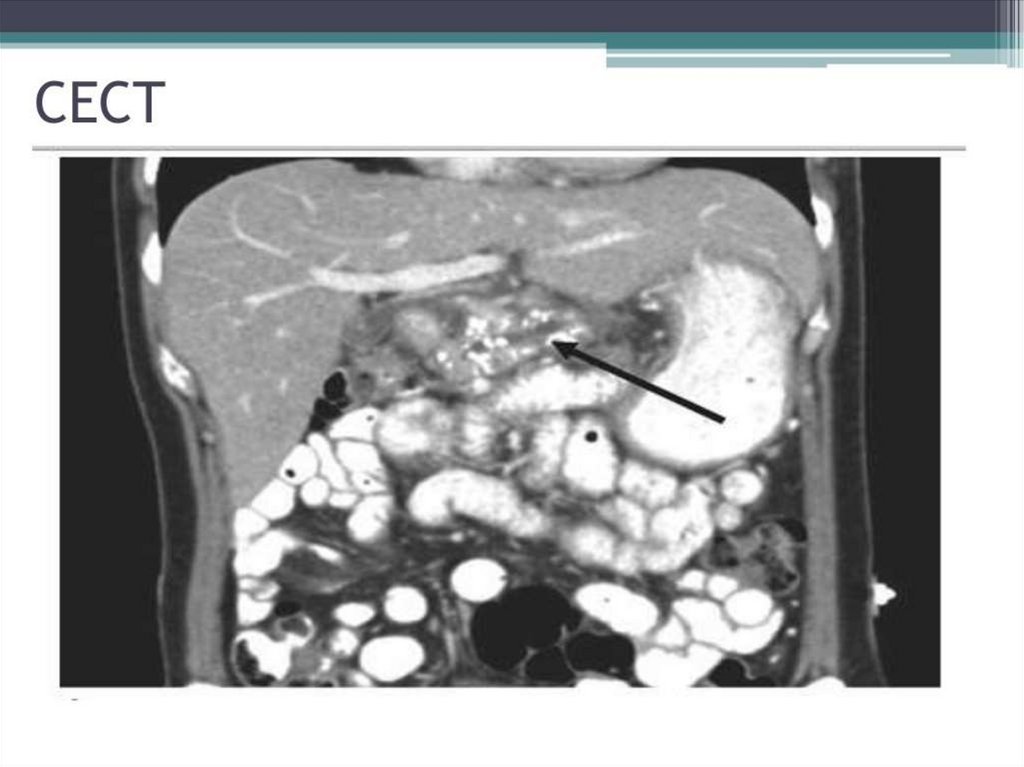

Chronic pancreatitis